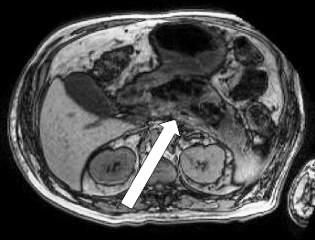

The physical examination was unremarkable except for a blood pressure of 80/60 mm Hg, which corrected with infusion of 2 L of normal saline. Laboratory findings included normal values for a complete blood cell count, complete metabolic panel, and serum amylase/lipase. CT of the abdomen and magnetic resonance cholangiopancreatography revealed acute emphysematous pancreatitis with extensive pancreatic necrosis (> 60%), without evidence of gallbladder or biliary tract disease (Figures 1 and 2).

Figure 2